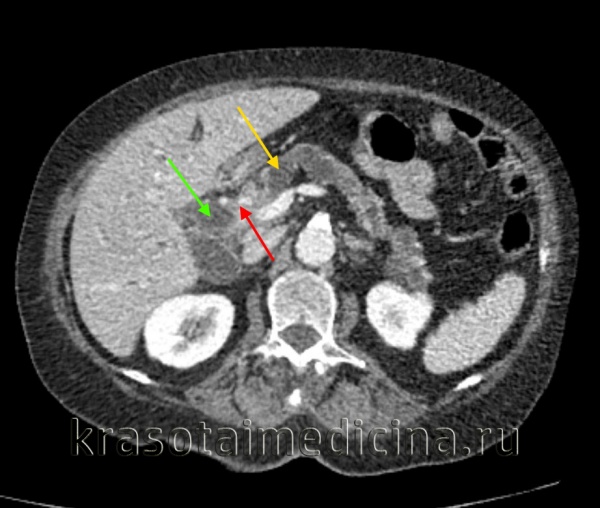

(Слева) На аксиальной КТ с контрастным усилением определяется рак желчного пузыря с инвазией в печень и нисходящую часть двенадцатиперстной кишки. Такие опухоли, если признаются резектабельными, однозначно требуют выполнения расширенной холецистэктомии и радикальной резекции.

(Справа) На аксиальной КТ с контрастным усилением визуализируется объемное образование в ямке желчного пузыря, прорастающее в печень. Во многих случаях, в том числе и в этом, место происхождения опухоли сложно определить.

КТ ОБП. Внутрипротоковая холангиокарцинома (опухоль Клацкина) холедоха (красная стрелка). Расширенный холедох (зеленая стрелка). Расширенный главный панкреатический проток (желтая стрелка).

КТ ОБП (этот же пациент). Опухоль Клацкина холедоха (красная стрелка). Расширенный просвет холедоха до зоны обструкции (зеленая стрелка).